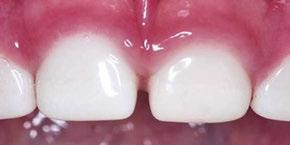

Case 3

A 4-year-old female presented with existing Silver Modified Atraumatic Restorative Technique (SMART) style restorations on #D, #E, #F, #G, and caries on other teeth. These anterior lesions

had been previously treated using SDF and covered with a HVGIC in a strip crown form. Though her lesions were stable from the clinical success of the SDF and HVGIC, these restorations were starting to fracture and demonstrate loss of material. The family wanted a more esthetic treatment option that would have a longer survivability. Additionally due to her high caries risk nature, a full coverage restoration with NuSmile® ZR anterior crowns were a more ideal solution in stabilizing her extensive decay pattern and covering staining from SDF therapy (Figure 4).

Figure 3: NuSmile® ZR Crowns were selected as a cementable full coverage restoration. At 6-month recall, apical tissues were healed with excellent gingival health Figure 4: SMART style restorations that were definitively restored with NuSmile® ZR Crowns as an esthetic option to cover SDF staining